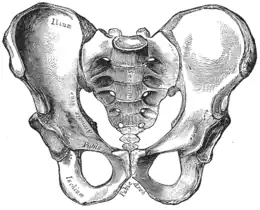

En anatomie le bassin osseux (en latin pelvis) est une partie du squelette humain, en forme d'entonnoir, constitué des deux os coxaux latéraux, du coccyx et du sacrum en arrière. Il constitue la limite squelettique de la cavité pelvienne et de la ceinture pelvienne.

Le bassin est constitué de plusieurs éléments :

- un élément central et postérieur : la partie caudale de la colonne vertébrale fixe constituée du sacrum et du coccyx ;

- deux os pairs et symétriques : les os coxaux. Ils sont chacun constitués de trois os qui se soudent entre eux vers l'âge de 12 ans. Cette soudure forme un Y au niveau de la fosse acétabulaire. Ces trois os sont :

- l'ilium est la partie supérieure (haute) de la soudure en forme de Y, c'est ce que l'on appelle communément la hanche ;

- l'ischium est la partie inféro-dorsale (basse dirigée en arrière) de la soudure en forme de Y, la partie la plus basse de l'ischium est la tubérosité ischiatique (c'est l'os sur lequel on s'assoit) ;

- le pubis est la partie inféro-ventrale (basse dirigée en avant) de la soudure en forme de Y, c'est la partie osseuse située au-dessus du sexe, ou bien l'endroit où se situent les poils pubiens, chez l'adulte ;

L'ischium et les branches ischio-pubienne et supérieure du pubis forme un orifice osseux : le foramen obturé.

L'ilium forme une grande aile : l'aile iliaque.

L'épine ischiatique délimite deux ouvertures : la grande incisure ischiatique et la petite incisure ischiatique.

Les deux os coxaux sont unis :

- au sacrum par les deux articulations sacro-iliaques en arrière ;

- entre eux par la symphyse pubienne en avant qui n'a qu'une petite possibilité de mouvement (quelques millimètres) pour amortir les mouvements de la marche.

Le bassin présente une forme de sablier avec un évasement supérieur développé et un évasement inférieur moins développé, séparés par une zone rétrécie appelée le détroit supérieur.

Il donne attache sur les côtés aux membres inférieurs par les articulations coxo-fémorales (hanche) entre le cotyle et la tête fémorale. Cette articulation se fait via une cavité articulaire située au centre de l'os coxal : l'acétabulum qui reçoit la tête fémorale.

La ligne arquée part de l'avant de l'ilium vers le pubis et se rattache à la symphyse pubienne. Elle délimite les organes de l'abdomen et ceux du petit bassin ou pelvis et détermine le détroit supérieur du passage de la tête fœtale lors de l'accouchement.